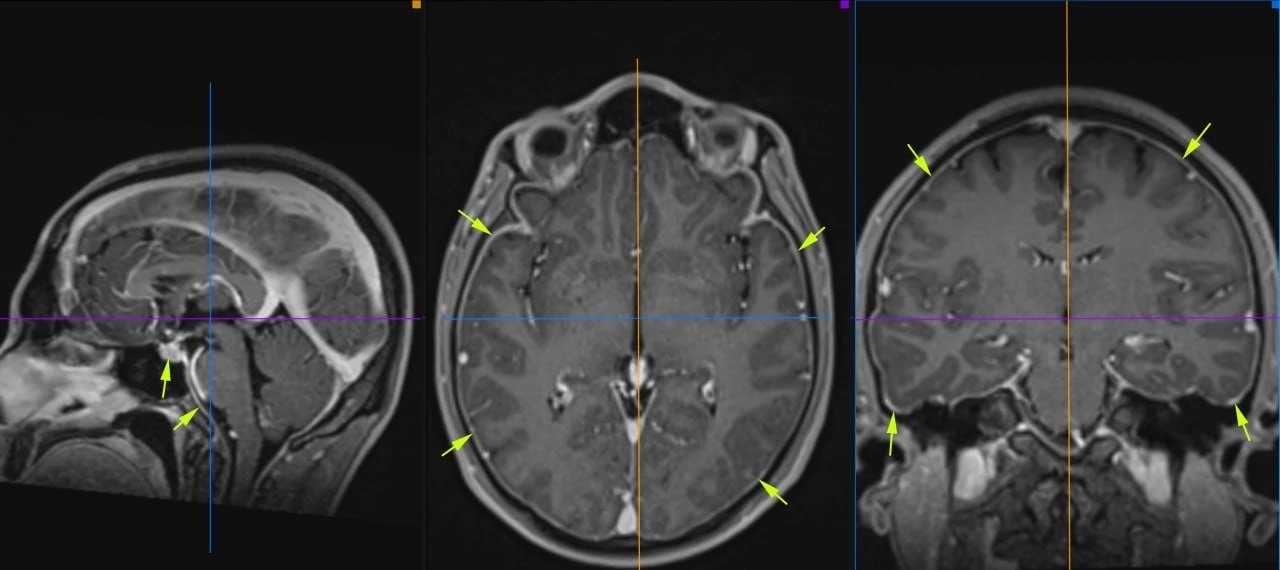

Женщина 32 года. Больной считает себя с 2024 г, когда стала отмечать онемение угла рта. Со слов пациентки ей был предварительно выставлен диагноз - РС, но дополнительных методов обследования и специфического лечения не проводилось. В настоящее время жалоб нет. В исследовании от октября 2024 отмечался очаг в левой затылочной доле с выраженным контрастированием, в настоящее время этот же очаг отмечается с сохраняющимся контрастированием. Формально - есть выполнение критериев диссеминации и в пространстве (юкстакортикальный и перивентрикулярный очаги есть), и во времени (есть усиливающиеся и неусиливающиеся очаги), клиника тоже вполне укладывается. Но! Найти в литературе подобных случаев мне не удалось, видел сам и максимум, что находил в литературе - полгода контрастирования. Получается, мы имеем дело с крайне атипичным рассеянным склерозом, или это не рассеянный склероз. А тогда что? Сосудистая мальформация не вариант - на SWI не видать. Какая-то ганглиоглиома? А другие очаги тогда что? Есть соображения? Кстати, диффузия стойко повышенная, и на б1000 почти не видно (изо). На Т2 не меняется